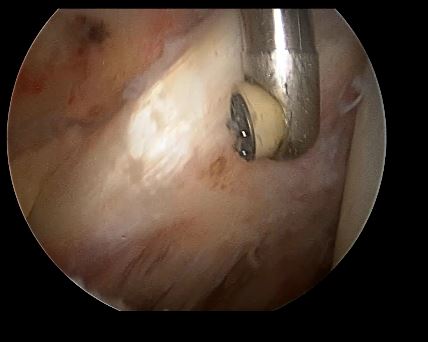

对于保守无效或者症状明显影响日程生活的可以行关节镜下微创清理松解肩关节(只需要2~3个0.5cm的小口子),改善肩关节活动度!

关节镜下可以彻底的清理关节内炎性滑膜组织及黏连带(盂肱关节及肩峰下关节)

入路处做2~3个0.5cm的小口子就可以微创手术,术后伤口愈合后基本看不见疤痕

清理后 ,肌腱活动度明显改善